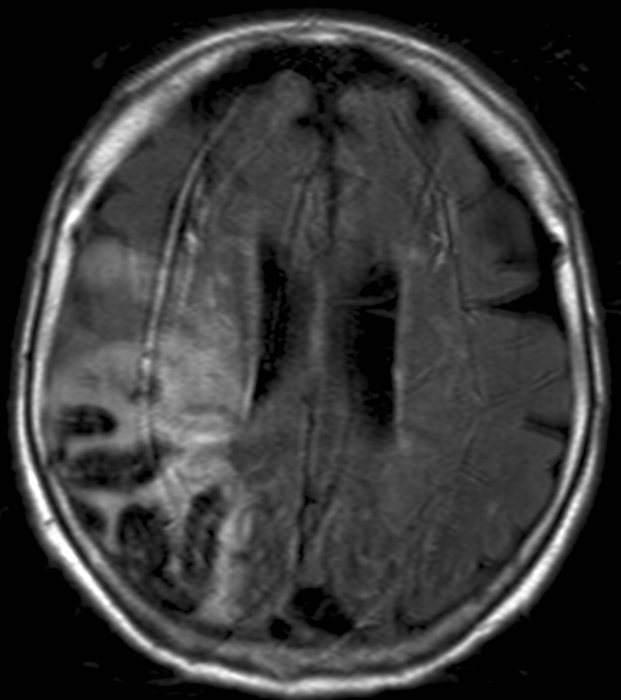

• Sinus thrombosis can occur in any of the intracranial sinuses. However, only cavernous sinus thrombosis constitutes a medical emergency. Facial, orbital, intracranial infections may be associated with sinus thrombosis. If available MRI is the method of choice to diagnose a suspected sinus thrombosis, or similar to other vascular diseases a contrast enhanced CT should be performed (MR and CT venography). Otogenic processes (e.g. mastoiditis) are frequently complicated with thrombosis of the sigmoid sinus.

13. Old woman with headache and altered mental status. Unenhanced and contrast enhanced CT scans show a hypodense lesion with gyral hyperdensity The location does not correspond to any arterial territories. On MRI it proved to be a bleeding. Lack of enhancement in the right transverse sinus indicates thrombosis.